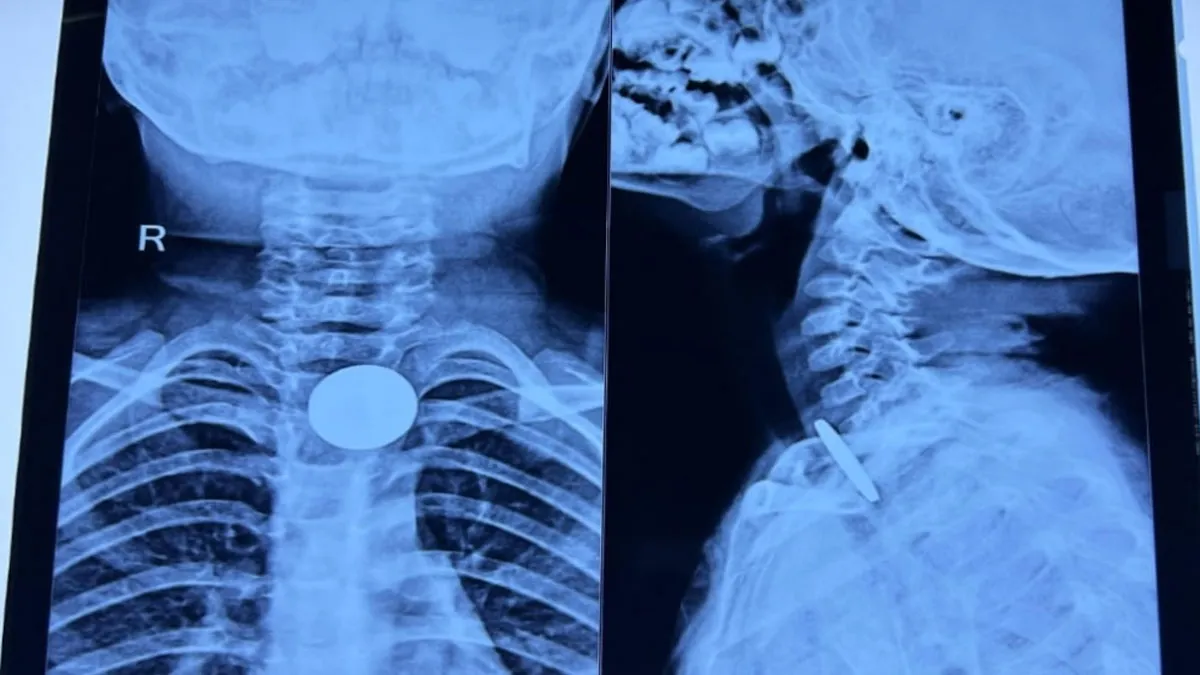

ਜਾਗਰਣ ਸੰਵਾਦਦਾਤਾ, ਅਲਮੋੜਾ: ਸੋਮੇਸ਼ਵਰ ਖੇਤਰ ਦੀ ਤਿੰਨ ਸਾਲਾ ਬੱਚੀ ਸੰਧਿਆ ਦੇ ਗਲੇ ਵਿੱਚ ਫਸੇ ਸਿੱਕੇ ਨੂੰ ਡਾਕਟਰਾਂ ਨੇ ਸਮਾਂ ਰਹਿੰਦੇ ਸਫਲਤਾਪੂਰਵਕ ਕੱਢ ਕੇ ਇੱਕ ਵੱਡੀ ਅਨਹੋਣੀ ਨੂੰ ਟਾਲ ਦਿੱਤਾ। ਪ੍ਰਾਪਤ ਜਾਣਕਾਰੀ ਅਨੁਸਾਰ, ਸੋਮੇਸ਼ਵਰ ਨਿਵਾਸੀ ਸ਼੍ਰੀ ਮੋਹਨ ਰਾਮ ਦੀ ਬੇਟੀ ਸੰਧਿਆ ਨੇ ਖੇਡਦੇ ਸਮੇਂ ਗਲਤੀ ਨਾਲ ਇੱਕ ਵਿਦੇਸ਼ੀ ਸਿੱਕਾ ਨਿਗਲ ਲਿਆ ਸੀ। ਇਸ ਤੋਂ ਬਾਅਦ ਬੱਚੀ ਨੂੰ ਤੁਰੰਤ ਕਮਿਊਨਿਟੀ ਹੈਲਥ ਸੈਂਟਰ (CHC) ਸੋਮੇਸ਼ਵਰ ਲਿਜਾਇਆ ਗਿਆ, ਜਿੱਥੇ ਮੁਢਲੀ ਜਾਂਚ ਤੋਂ ਬਾਅਦ ਉਸਦੀ ਹਾਲਤ ਗੰਭੀਰ ਦੇਖਦੇ ਹੋਏ ਉਸਨੂੰ ਹਾਇਰ ਮੈਡੀਕਲ ਸੈਂਟਰ ਰੈਫਰ ਕਰ ਦਿੱਤਾ ਗਿਆ।

ਹਸਪਤਾਲ ਪਹੁੰਚਣ 'ਤੇ ਬੱਚੀ ਦੇ ਗਲੇ ਦਾ ਦੁਬਾਰਾ ਐਕਸ-ਰੇ ਕੀਤਾ ਗਿਆ। ਜਾਂਚ ਵਿੱਚ ਸਿੱਕਾ ਕ੍ਰਿਕੋਫੈਰਿਨਕਸ (cricopharynx) ਦੇ ਕੋਲ ਫਸਿਆ ਹੋਇਆ ਪਾਇਆ ਗਿਆ, ਜੋ ਕਿ ਬਹੁਤ ਖ਼ਤਰਨਾਕ ਸਥਿਤੀ ਮੰਨੀ ਜਾਂਦੀ ਹੈ। ਮਾਮਲੇ ਦੀ ਗੰਭੀਰਤਾ ਨੂੰ ਦੇਖਦੇ ਹੋਏ ਤੁਰੰਤ ਐਮਰਜੈਂਸੀ ਓਪਰੇਸ਼ਨ ਥੀਏਟਰ (OT) ਨੂੰ ਸੂਚਿਤ ਕੀਤਾ ਗਿਆ ਅਤੇ ਓਪਰੇਸ਼ਨ ਤੋਂ ਪਹਿਲਾਂ ਦੀਆਂ ਸਾਰੀਆਂ ਜ਼ਰੂਰੀ ਕਾਰਵਾਈਆਂ ਪੂਰੀਆਂ ਕੀਤੀਆਂ ਗਈਆਂ।

ਓਪਰੇਸ਼ਨ ਦੌਰਾਨ ਬੱਚੀ ਨੂੰ ਬੇਹੋਸ਼ੀ (general anesthesia) ਦਿੱਤੀ ਗਈ। ਈਸੋਫੈਗੋਸਕੋਪੀ (esophagoscopy) ਪ੍ਰਕਿਰਿਆ ਰਾਹੀਂ ਸਿੱਕੇ ਨੂੰ ਪੂਰੀ ਸਾਵਧਾਨੀ ਨਾਲ ਸੁਰੱਖਿਅਤ ਬਾਹਰ ਕੱਢ ਲਿਆ ਗਿਆ। ਪ੍ਰਕਿਰਿਆ ਤੋਂ ਬਾਅਦ ਬੱਚੀ ਦੀ ਹਾਲਤ ਤਸੱਲੀਬਖਸ਼ ਪਾਈ ਗਈ।